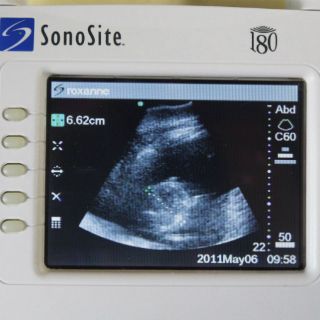

WASHINGTON, ESTADOS UNIDOS (17/SEP/2014).- Los estudios de ultrasonido son igual de eficientes que las

tomografías computarizadas para hallar piedras renales y deberían ser usados con este fin para evitar una exposición innecesaria a la radiación, dijeron investigadores el miércoles.

Algunos fueron examinados con ultrasonido por un doctor de la emergencia, otros con ultrasonido por un médico especializado y otros fueron sometidos a una tomografía computarizada por parte de un radiólogo.